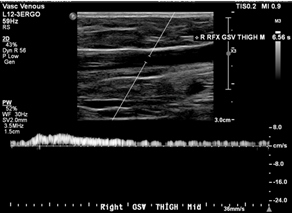

Case: 35F presented with painful right posteromedial thigh and knee vein, concerned for thrombosis given history of DVT in both parents. However, duplex ultrasound was unremarkable with no clots or reflux, and the patient was treated conservatively with compression stockings. She returned 6 years later noting leg fatigue worse at the end of nursing shifts. A repeat duplex performed 6 months earlier showed axial reflux in the right great saphenous and small saphenous veins (Figure 1).

Images showed questionable reflux and it was revealed that the study was performed in a moderate reverse Trendelenburg (RT) position. There was mild reflux at the SFJ in response to Valsalva and a long duration reflux in the thigh and leg in response to distal augmentation with the signal becoming intermittent distally.

Investigation: A low amplitude reflux could cause this pattern with gaps in reflux representing amplitude dipping below the detectable or filtered threshold. However, this could also represent a failure of RT position to generate sufficient downward pressure to achieve complete valve closure, which can result in a valve fluttering effect as blood passes through. We repeated the duplex ultrasound with the patient standing, and this was negative for reflux in any GSV segment.

Discussion: Optimal assessment of venous reflux with duplex imaging requires upright positioning. Tthis serves as a reminder that supine and even RT positioning can cause false positive results in addition to false negatives. Steep RT can provide accurate results and ease the ergonomic burden on technologists, but any questionable results should be double-checked in the standing position.